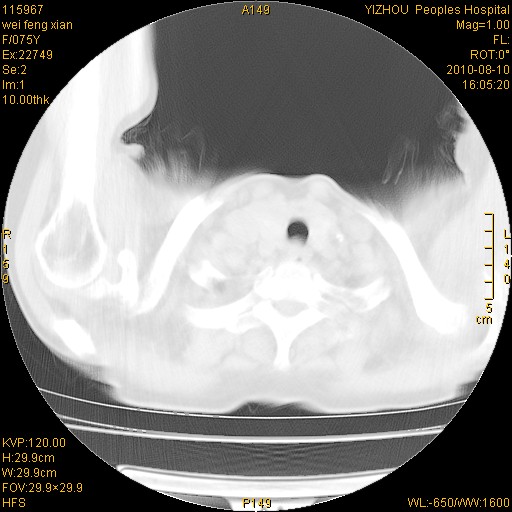

标题: CT28313:两肺弥漫性病变 [打印本页]

标题: CT28313:两肺弥漫性病变

女,75岁,患者反复头昏乏力面色苍白3年,再发10天入院。临床贫血查因。